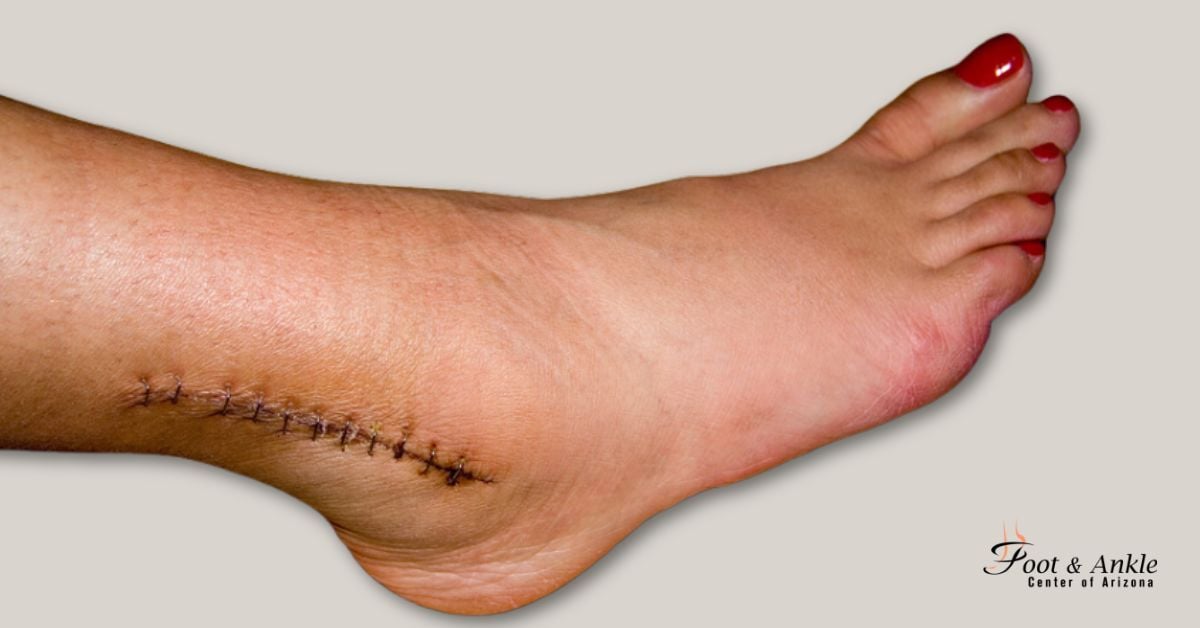

When a fibula or tibia is fractured, it can heal with a stable internal fixation screwed onto the bone during surgery to help align the bones properly. This will take a few weeks and patients should avoid weight on their ankle for 3 to 10 weeks, depending on the severity of the fracture. In addition, patients should wear a cast or boot and also attend physical therapy for optimal results.

Achilles tendon injuries include ruptures, tears, and even acute tendonitis. When these injuries do not respond to traditional treatment options such as rest, ice, medications, orthotics, and physical therapy, then is needed.

When is needed to treat your ankle injury, the Foot and Ankle Center of Arizona provides you with the finest foot and ankle care to get you back on your feet, using only the highest quality equipment and provides the leading surgical techniques to help you find relief.